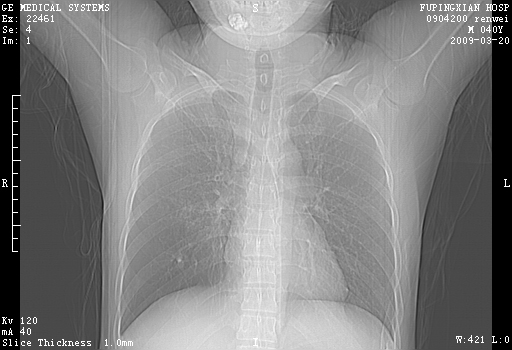

标题: CT18920:平时体健,体检时发现以下问题。

单侧肺气肿表现,原因?   特发性或先天性可能

右肺气肿。

右肺局限性肺气肿

右肺局限性肺气肿。

右肺局限性肺气肿,有无呛咳史?

双肺弥漫磨玻样改变,肺纹理增重,考虑早期间质纤维化伴局部阻塞肺气肿,[考虑黏液栓]

右肺局限性肺气肿;[考虑黏液栓]所致。

双肺弥漫磨玻样改变,右肺局限性肺气肿。病人没有症状?

考虑间质性肺炎伴右侧局限性肺气肿,

先天性支气管闭锁

右肺局限性肺气肿,原因?先天支气管闭锁?粘液栓?